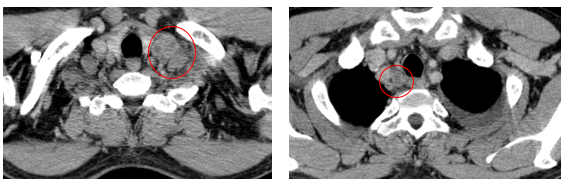

-         Chụp cắt lớp vi tính lồng ngực (08/2025): Khối rốn phổi trái ôm quanh nhánh phế quản thùy dưới trái kích thước 28x26mm, dày tổn chức kẽ vách liên tiểu thùy và nhiều nốt đặc lan tỏa khắp nhu mô, đường kính <7mm. Màng phổi trái có vài nốt đặc ngấm thuốc nốt lớn nhất kích thước 17x15mm  Khoang màng phổi trái có dịch dày 54mm. Nhiều hạch to trung thất, rốn phổi hai bên và hố thượng đòn có hoại tử trung tâm, hạch lớn nhất kích thước trục ngắn 22mm.

Hình 01: Nhiều hạch to trung thất, rốn phổi hai bên và hố thượng đòn có hoại tử trung tâm, hạch lớn nhất kích thước trục ngắn 22mm

-         Siêu âm hạch vùng cổ (11/2025): Góc hàm hai bên có vài hạch kích thước lớn nhất 6mm.

-         Chụp cắt lớp vi tính lồng ngực (11/2025): Màng phổi vùng rốn phổi trái dày,dày tổ chức kẽ vùng ngoại vi đáy phổi hai bên. Màng phổi trái có vài nốt đặc ngấm thuốc nốt lớn nhất kích thước 17x15mm. Khoang màng phổi hai bên không có dịch – khí (Tổn thương giảm đáng kể so với phim chụp 08/2025). Trung thất, rốn phổi hai bên, hố thượng đòn trái có vài hạch, hạch lớn nhất kích thước 12x6mm. Vài nốt đặc xương rải rác thân đốt sống, các cung xương sườn hai bên.

Hình 07: Hạch thượng đòn trái giảm đáng kể kích thước, từ 22mm còn 7mm sau điều trị.

+    Hạch trung thất và thượng đòn: giảm kích thước rõ rệt, nhiều hạch không còn quan sát được trên phim chụp.